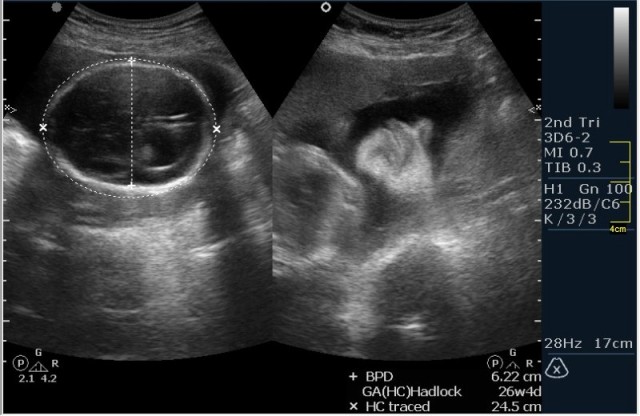

Женщина 23 года; из глухой деревни. К врачу обращалась один раз, когда забеременела. Дату последних месячных не помнит. Gravida 2, para 0. Направлена гинекологом для определения точного срока беременности и состояния плода.

1.Вентрикуломегалия/гидроцефалия (на сонограмме №1 размер задних рогов боковых желудочков 16мм при норме до 10 мм включительно;

На сонограммах головы плода визуализаируется гифдроцефалия, патогенетически связанная со спинномозговой грыжей (менингомиелоцеле) представленная в 2D и 3D режимах. В режиме Skeleton не удалось получить "картинку презентационного качества", плод начал сильно вертется; но рекоммендация очень грамотная :idea: , спасибо за ваш пост!